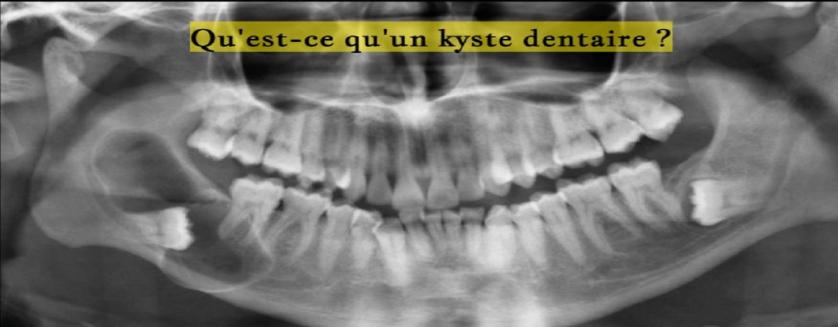

Qu'est-ce qu'un kyste dentaire ?

Le kyste est une tumeur puisqu’elle correspond bien à une augmentation de volume d’un tissu clairement délimitée sans précision de cause.